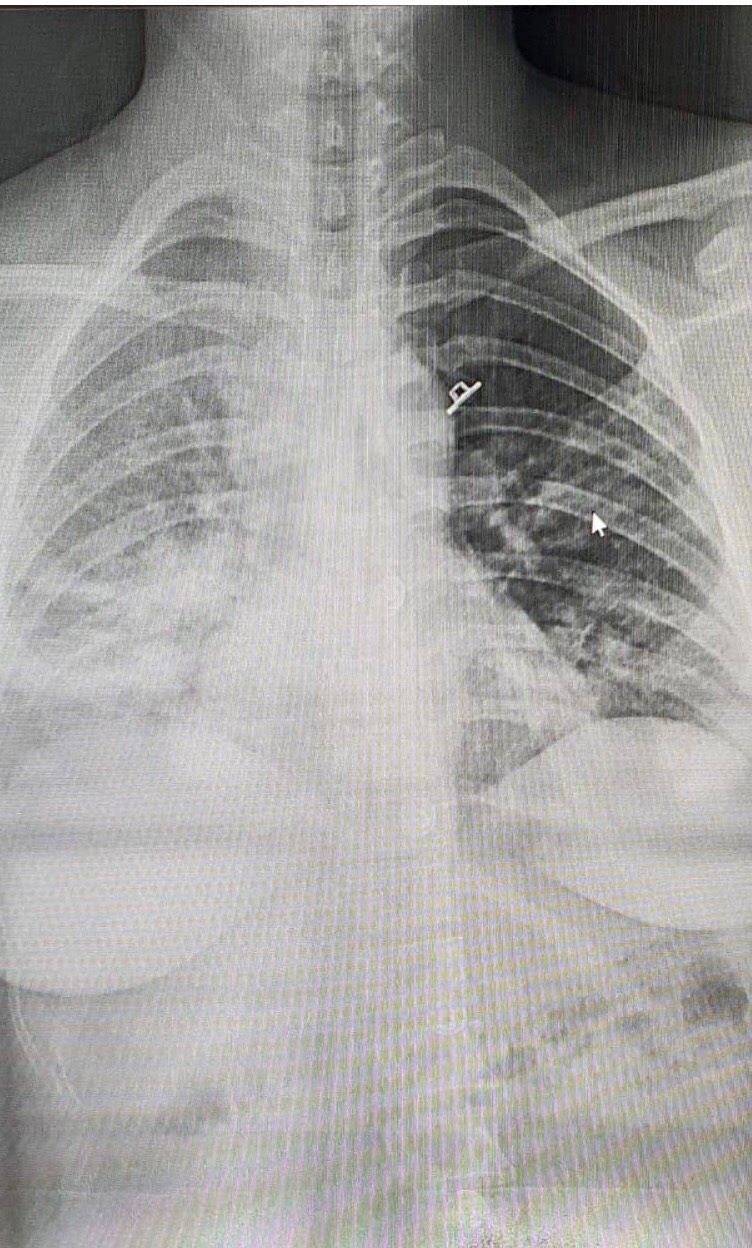

| Hình ảnh X-quang chụp phổi của bệnh nhân (Nguồn: Bộ Y tế Việt Nam) |

Tại thời điểm thăm khám vào sáng ngày 14/05/2021, bệnh nhân đang thở oxy mask túi, huyết động ổn định, nhịp thở 34 lần/phút, còn tức ngực, bụng to tương ứng tuổi thai, không ra dịch-máu âm đạo, hình ảnh phim chụp X-quang ngực của bệnh nhân có tổn thương dạng kẽ ở hai đáy phổi. Bệnh viện Pholthong đã thực hiện xét nghiệm tổng phân tích tế bào máu cho thấy tình trạng giảm bạch cầu dòng Lympho (Bạch cầu 7.18G/l, tỉ lệ Lympho là 0.6G/l) và giảm tiểu cầu (Tiểu cầu 134 G/l), các xét nghiệm chức năng thận cơ bản trong giới hạn bình thường. Hiện tại bệnh nhân đã được sử dụng kháng sinh đường tĩnh mạch, thuốc kháng virus và Dexamethasone.